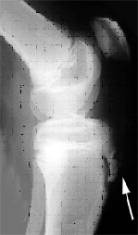

Inestabilidad fémoro patelar

Es una entidad clínica en la que se encuentra alterado en normal funcionamiento de esta articulación ocasionado por la descompensación de las estructuras retentoras de la misma (óseas y/o de partes blandas).

La sintomatología clínica es muy variada pudiendo manifestarse en forma de dolor rotuliano , subluxación y luxación de rótula , esporádica o inveterada , y fracturas osteocondrales asociadas a episodios de luxación. Deben valorarse detenidamente los estabilizadores óseos y músculo-ligamentosos que participan en el funcionamiento de esta articulación a la hora de plantearse el tratamiento de esta patología.

En los pacientes en edad pediátrica es muy frecuente la asociación de esta entidad a la presencia de un rótula alta (determinada por el índice de Insall) por lo que utilizamos la técnica descrita por Galleazzi mediante tenodesis con tendón semitendinoso autólogo y sección artroscópica del alerón rotuliano externo.